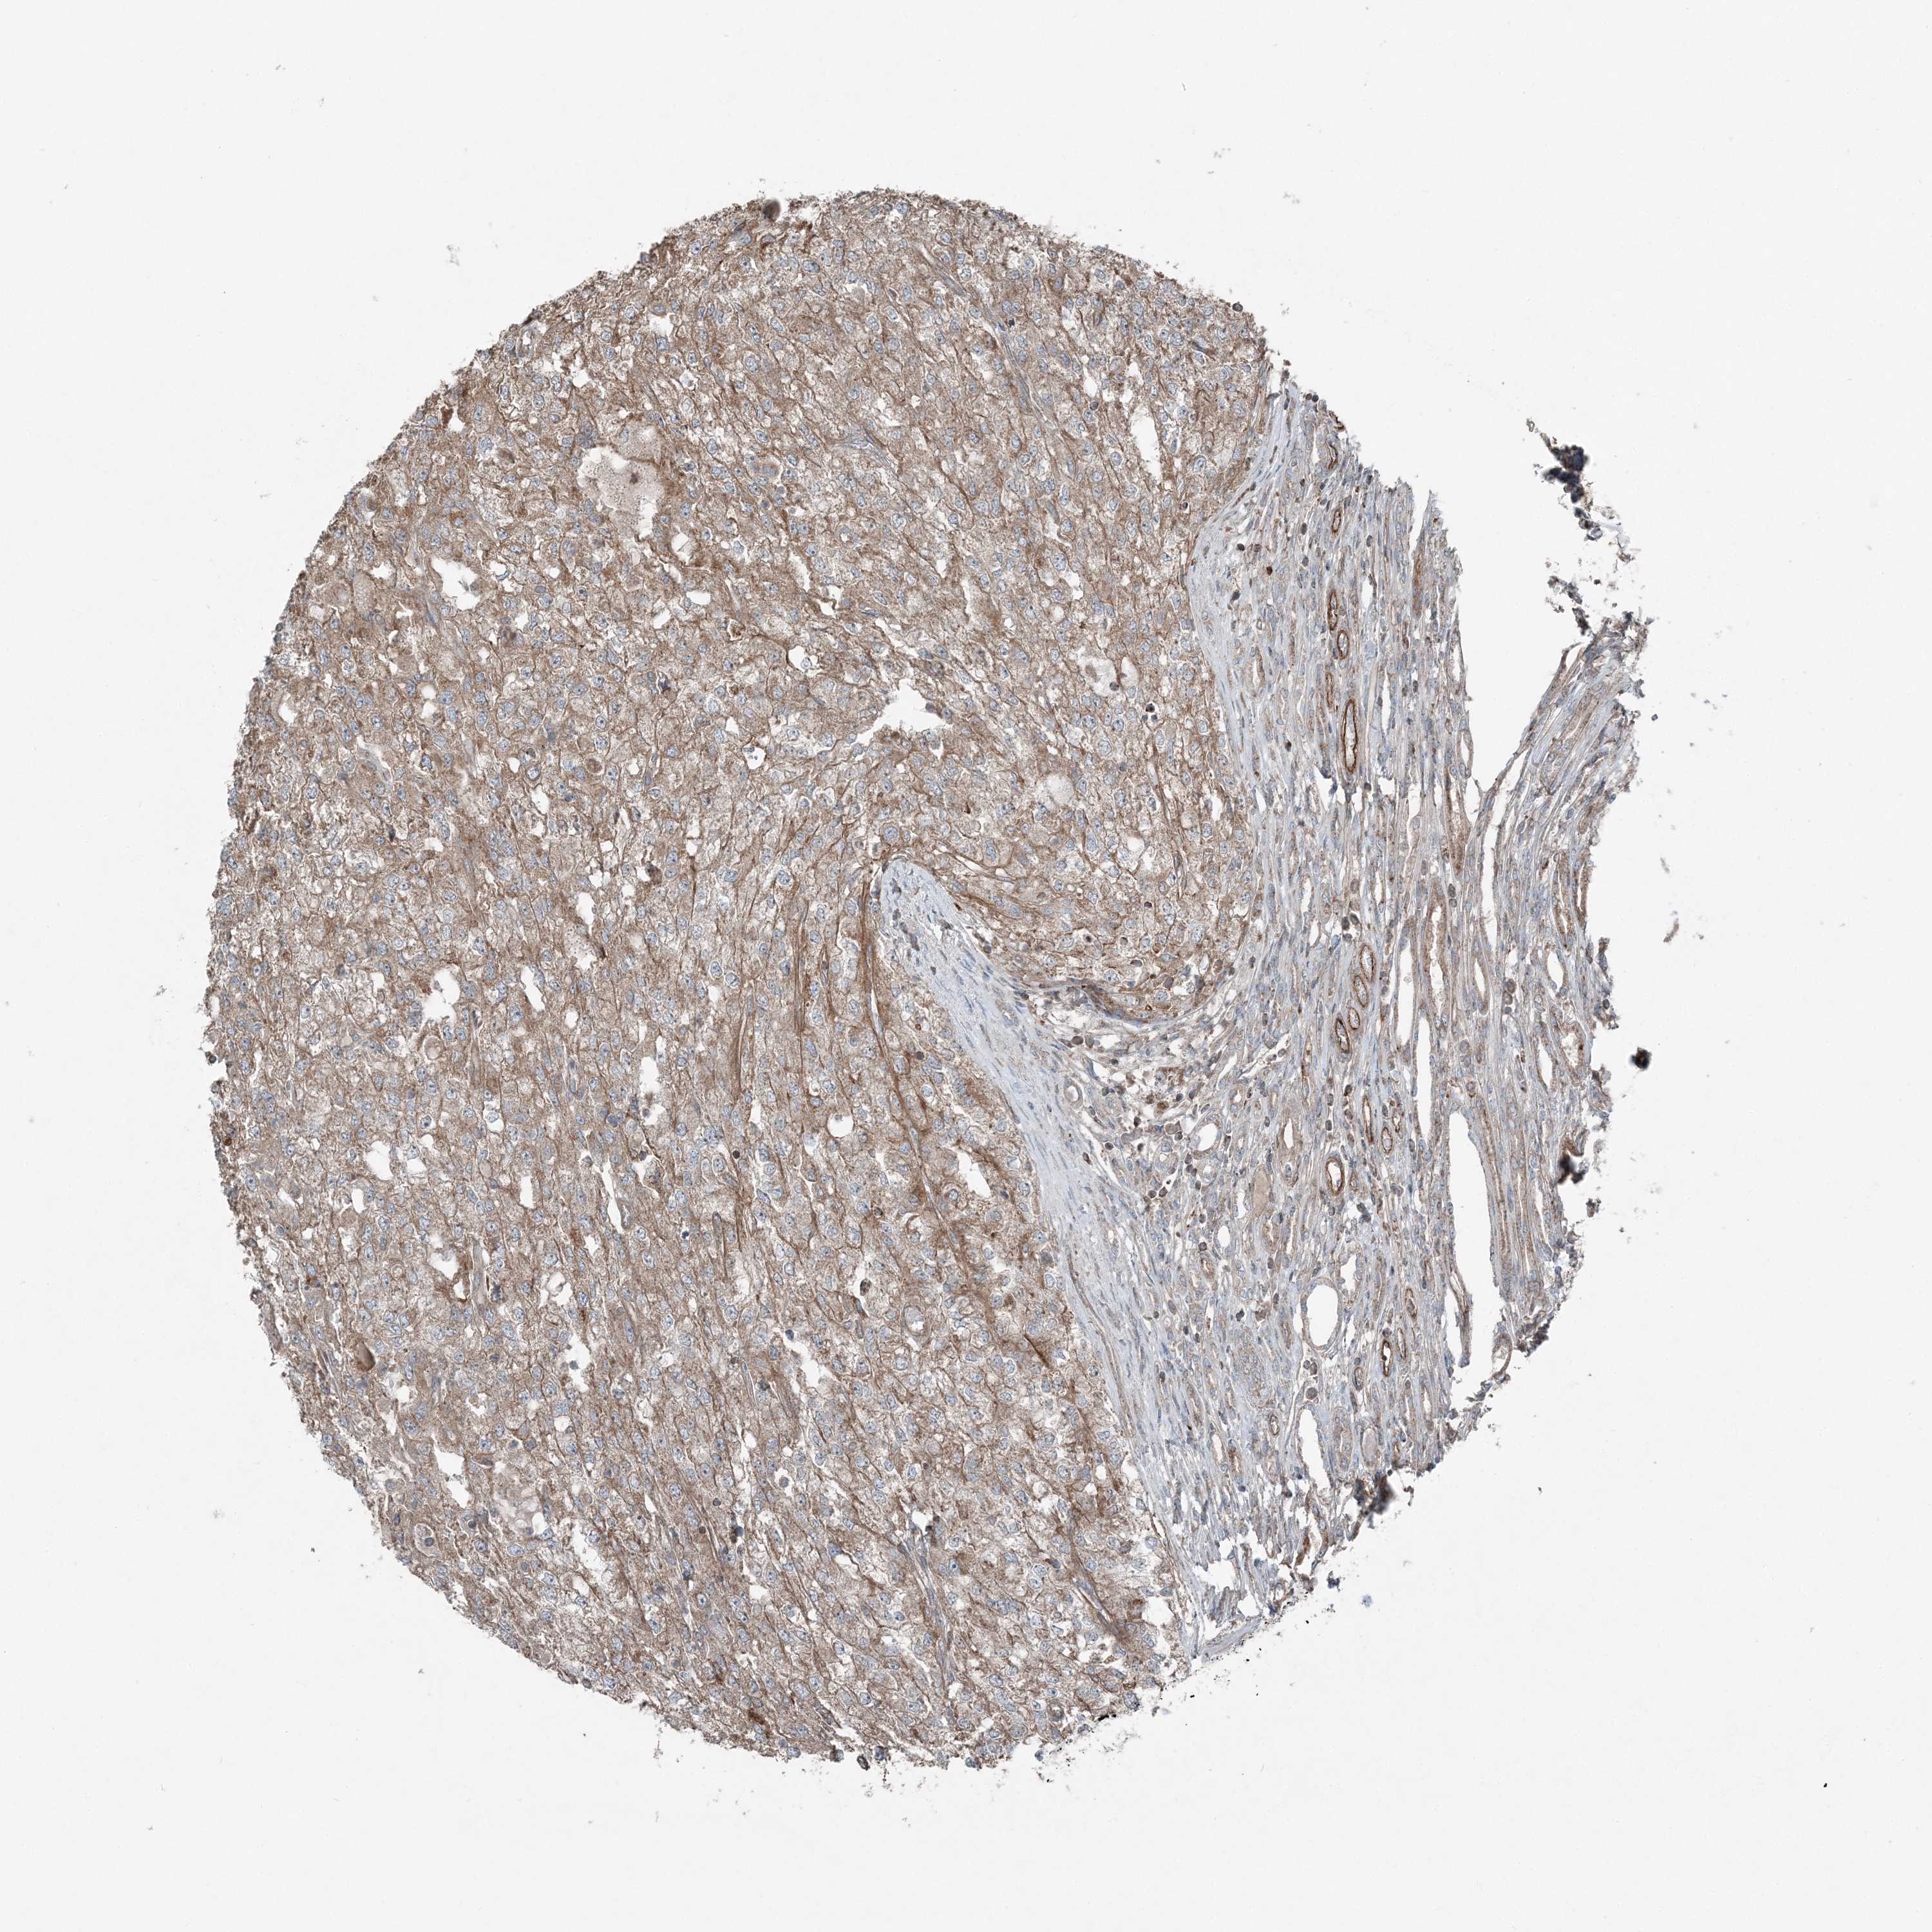

TCGA RNA samplesi

RNA-seq data is reported as average FPKM (number Fragments Per Kilobase of exon per Million reads), generated by the The Cancer Genome Atlas (TCGA) .

Normal distribution across the dataset is visualized with box plots, shown as median and 25th and 75th percentiles. Points are displayed as outliers if they are above or below 1.5 times the interquartile range. FPKM values of the individual samples are presented next to the box plot.

Average pTPM 0.3

Number of samples 100